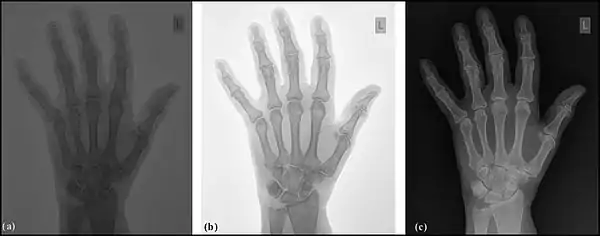

Image sampling is the process used to digitise the spatial information in an image. It is typically achieved by dividing an image into a square or rectangular array of sampling points - see the following figure. Each of the sampling points is referred to as a picture element - or pixel to use computer jargon. Although in the context of DR image receptors, the term detector element, or del, is also used. Naturally, the larger the number of pixels or dels, the closer the spatial resolution of the digitised image approximates that of the radiation pattern transmitted through the patient – see the following figure, panels (a) and (b).

The process may be summarised as the digitisation of an image into an N x N array of pixel data. Examples of values for N are 1024 for a angiography image, and 3,000 for a digital radiograph.

Note that each pixel represents not a point in the image but rather an element of a discrete matrix. Distance along the horizontal and vertical axes is no longer continuous, but instead proceeds in discrete steps, each given by the pixel size. With larger pixels, not only is the spatial resolution poor, since there is no detail displayed within a pixel, but grey-level discontinuities also appear at the pixel boundaries (pixelation) - see panel (b) in the figure. The spatial resolution improves with smaller pixels and a perceived lack of pixelation gives the impression of a spatially continuous image to the viewer.

Image quantisation is the process used to digitise the brightness information in an image. It is typically achieved by representing the brightness of a pixel by an integer whose value is proportional to the brightness. This integer is referred to as a 'pixel value' and the range of possible pixel values which a system can handle is referred to as the grey scale. Naturally, the greater the grey scale, the closer the brightness information in the digitised image approximates that of the original image – see the following figure, panels (a) and (c). The process can be considered as the digitisation of image brightness into G shades of grey. The value of G is dependent on the binary nature of the information coding. Thus G is generally an integer power of 2, i.e. G=2m, where m is an integer which specifies the number of bits required for storage. Examples of values of G are 1,024 (m=10) in fluoroscopy, 2,048 (m=11) in angiography and 4,096 (m=12) in digital radiography. Note that the slight difference between the brightness in an analogue image and its pixel value in the digital image is referred to as the quantisation error, and is lower at larger values of G.